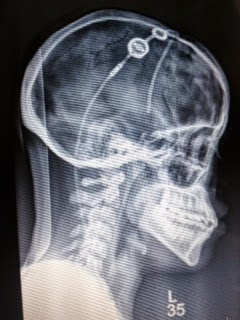

| X Ray image of my shunt 2014 to present. |

I had three days of pain free no drama from my shunt this week. Yesterday, barometric pressure headaches returned. Apparently, there is snow in the atmosphere expected later today. I’ve had episodes of dizziness since yesterday. The shunt is adjusting itself again and I feel distal catheter pain in my abdomen yesterday and today. Saturday morning around 11am was when I felt light throbbing from my shunt valve at the top of my head. This happened while I was driving yesterday, which almost never happens. Today, besides the pressure in my forehead, there is some pain in the back of my head from the chiari malformation, I acquired during the shunt revision in 2009.